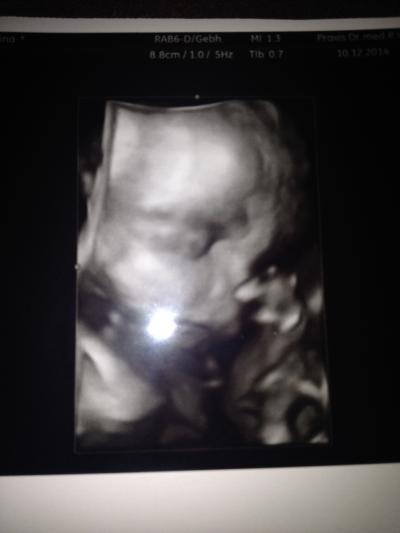

Also, heut war dann der Zuckertest, das Ergebnis bekomme ich morgen. Beim US war alles super, er saß in BEL und wir haben ein tolles Bild bekommen! Er soll jetzt c.a. 28cm groß sein (die gleiche Größe hatte seine Kollegin schon vor 4 Wochen gemessen) und 990g schwer sein. Kommentar des Arztes war: Der ist aber gut dabei! Sonst habe ich auch mein erstes CTG hinter mir, obwohl es eig nur ein TG war ;) Und im Urin waren Leukos, sodass eine Uricult angelegt wurde. Das Ergebnis dauert aber länger...

Bild zu Zurück von der Vorsorge! - Forum für März - Mamis

ui Glückwunsch, fast das Kg gepackt hoffe die Leukos sind nicht so schlimm. ein super Bild